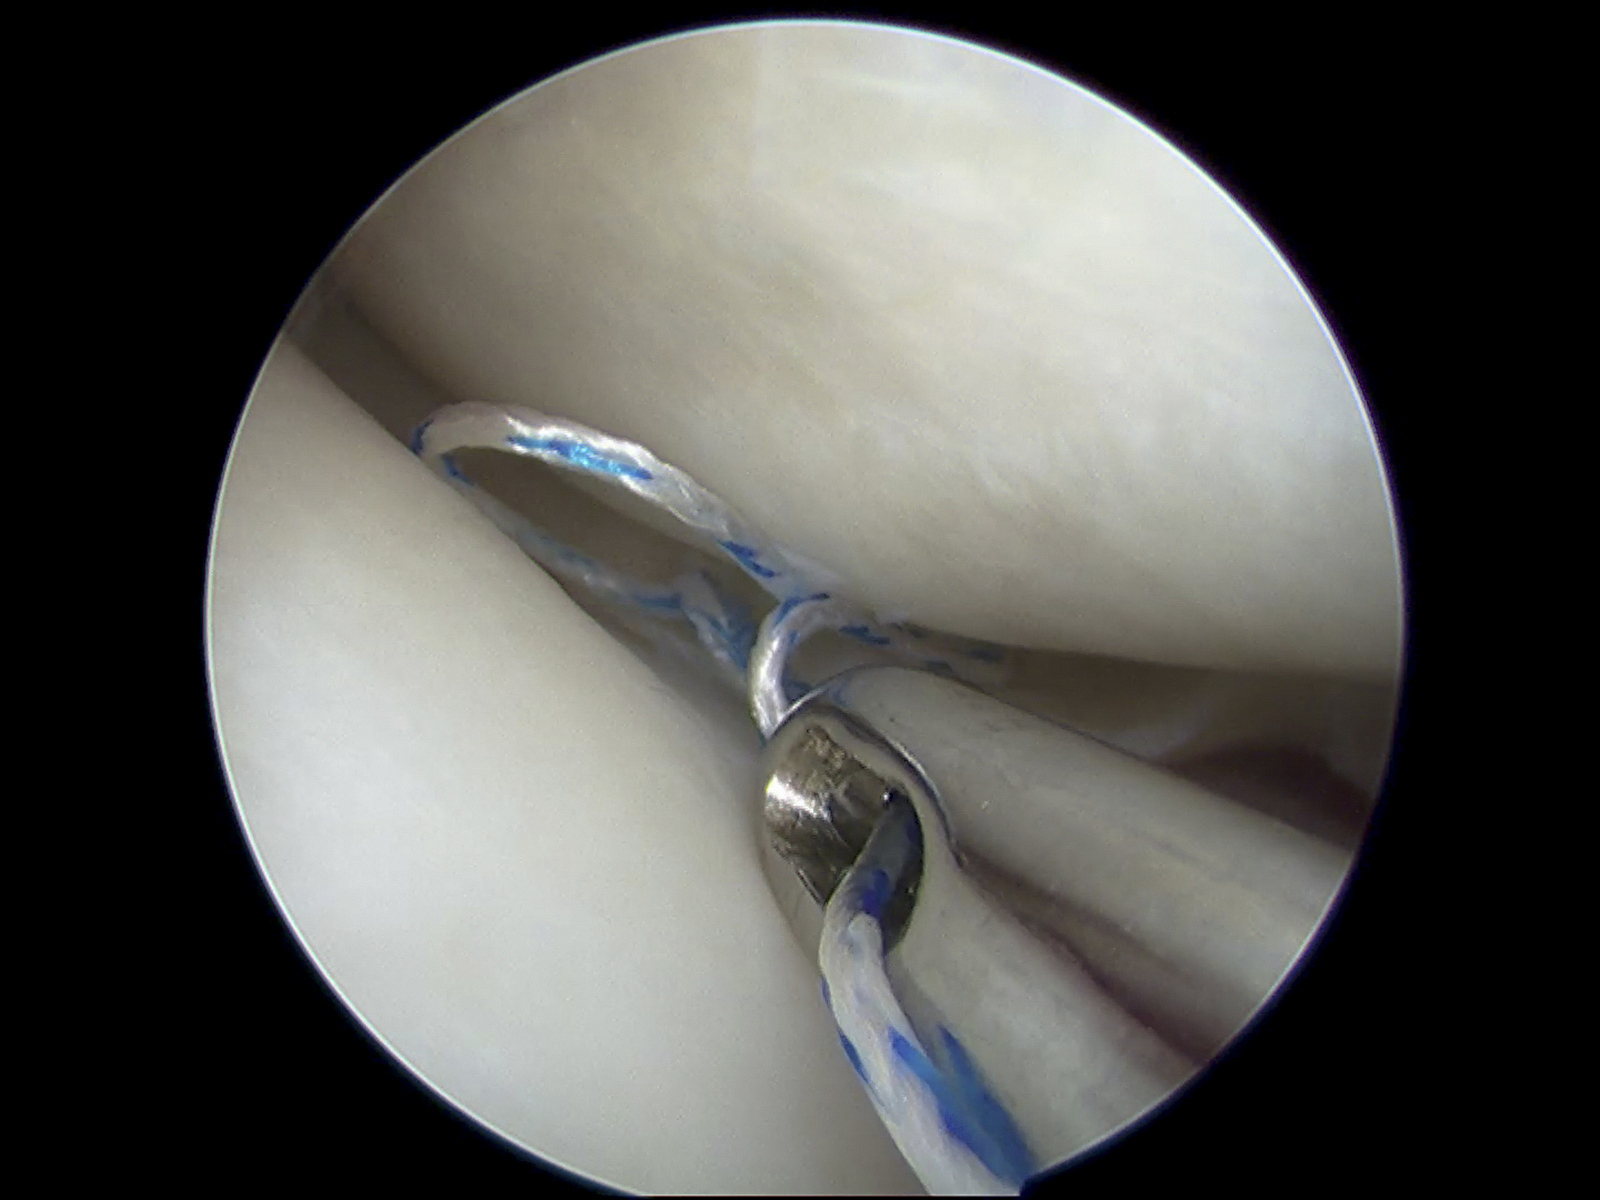

本研究使用关节镜技术对距腓前韧带进行修复,具有以下优势:

3. 关节镜手术仅使用两个入口,降低了滑膜损伤和过度水肿的风险,避免了广泛粘连的形成。

4. 关节镜手术可以直接观察踝关节,使医生能够在手术中同时发现和治疗伴随的关节内病变,如软组织撞击、关节游离体、骨赘或骨软骨损伤等。